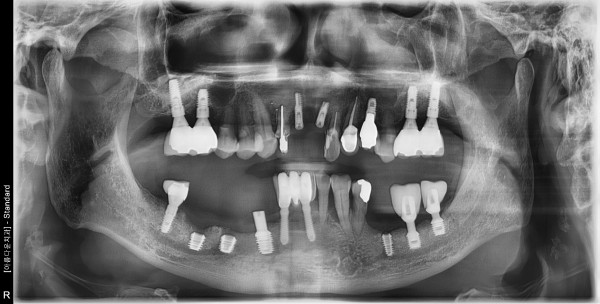

76세 남자 상악 전치부& 하악 구치부 발치 및 치조골이식술 후 임플란트 식립